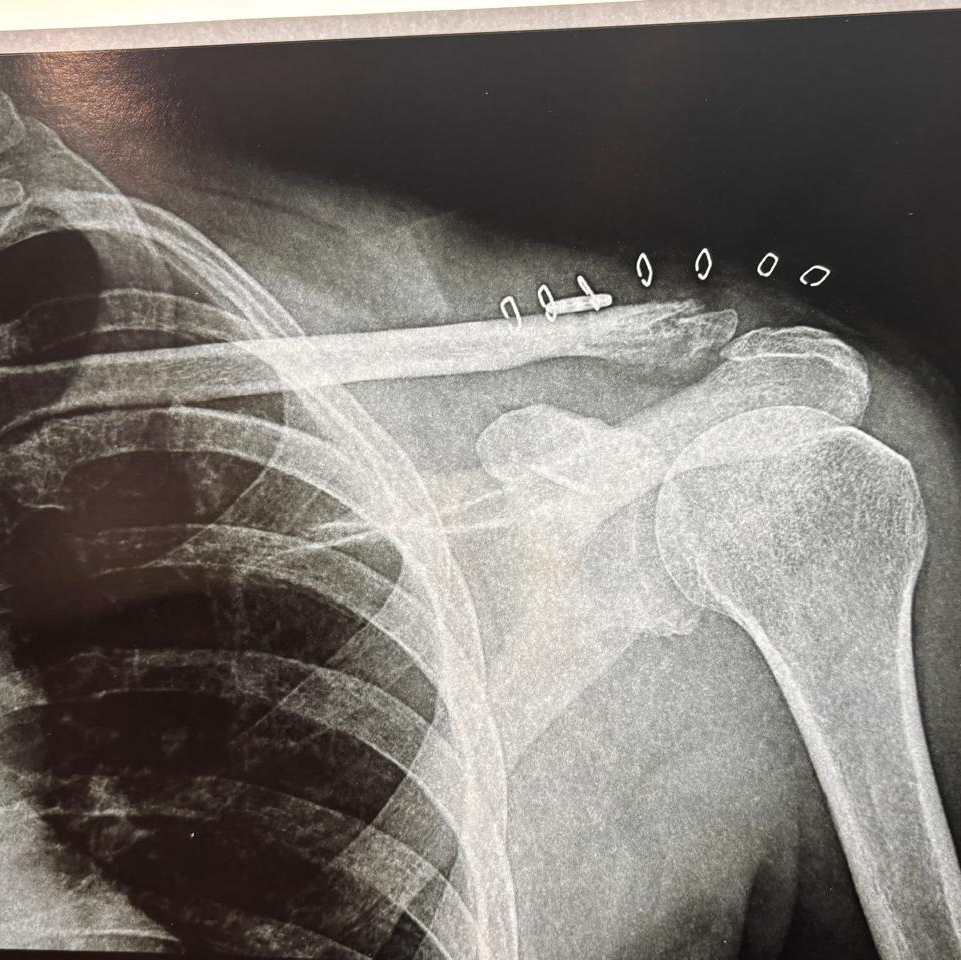

Fracture Clavicle operated successfully by fibre tape and Endobutton

A 50 years old male came to Dr Pankaj Ortho Centre with fracture lateral end left Clavicle with AC joint dislocation.

He was operated with fibre tape, fibre wire and Endo button technique by Dr Pankaj Kumar.

Rehabilitation was started and he recovered with pain free Range of motion.

Clavicle fracture is usually treated conservatively but lateral end clavicle fracture requires anatomical reduction as many ligaments are injured after this fracture.